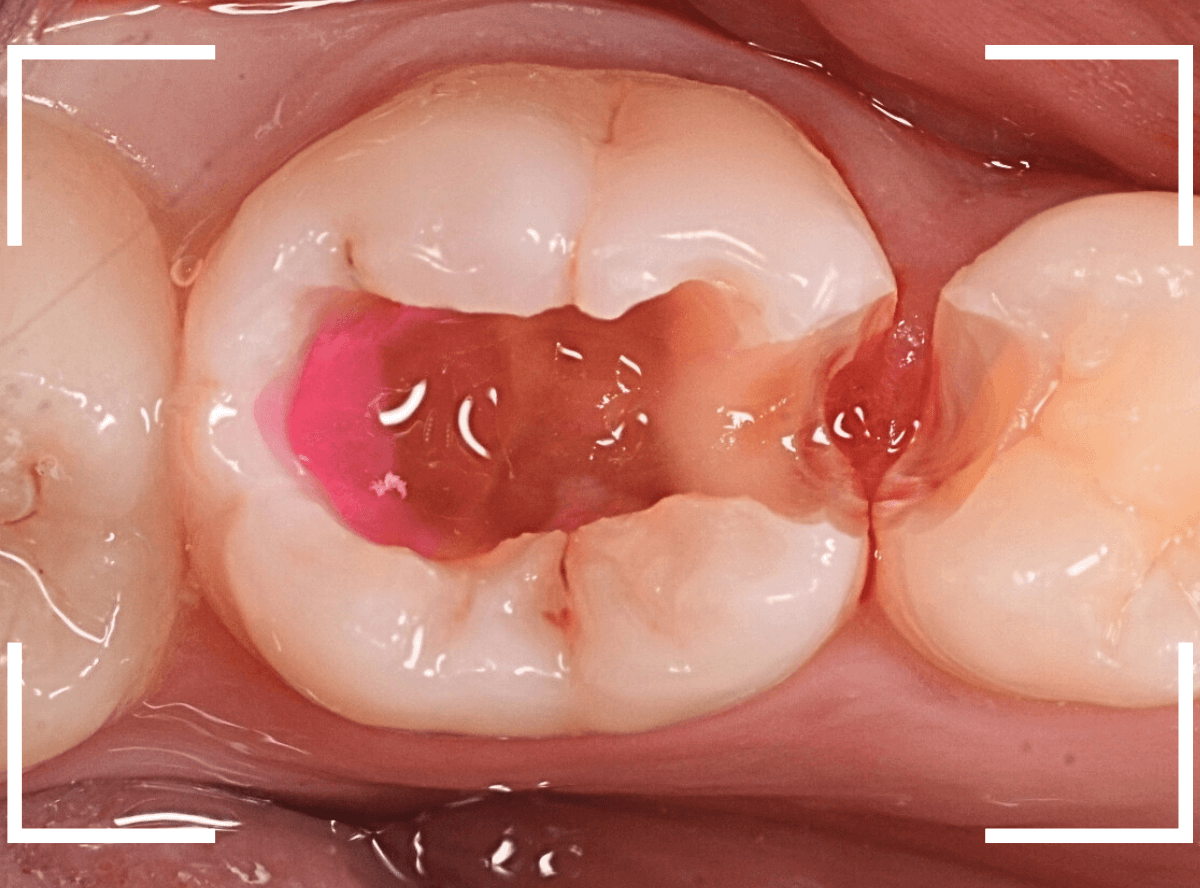

裂溝部分を少し削ると、中は虫歯で大きな空洞になっていました。

ある程度、虫歯を除去したところで、う蝕検知液で確認します。

真っ赤に染まり、まだ虫歯が取り切れていないのがわかります。

神経まで近づいてきたので、慎重に虫歯を除去します。

全ての虫歯を除去したところです。

神経スレスレのところまで虫歯が広がっていました。